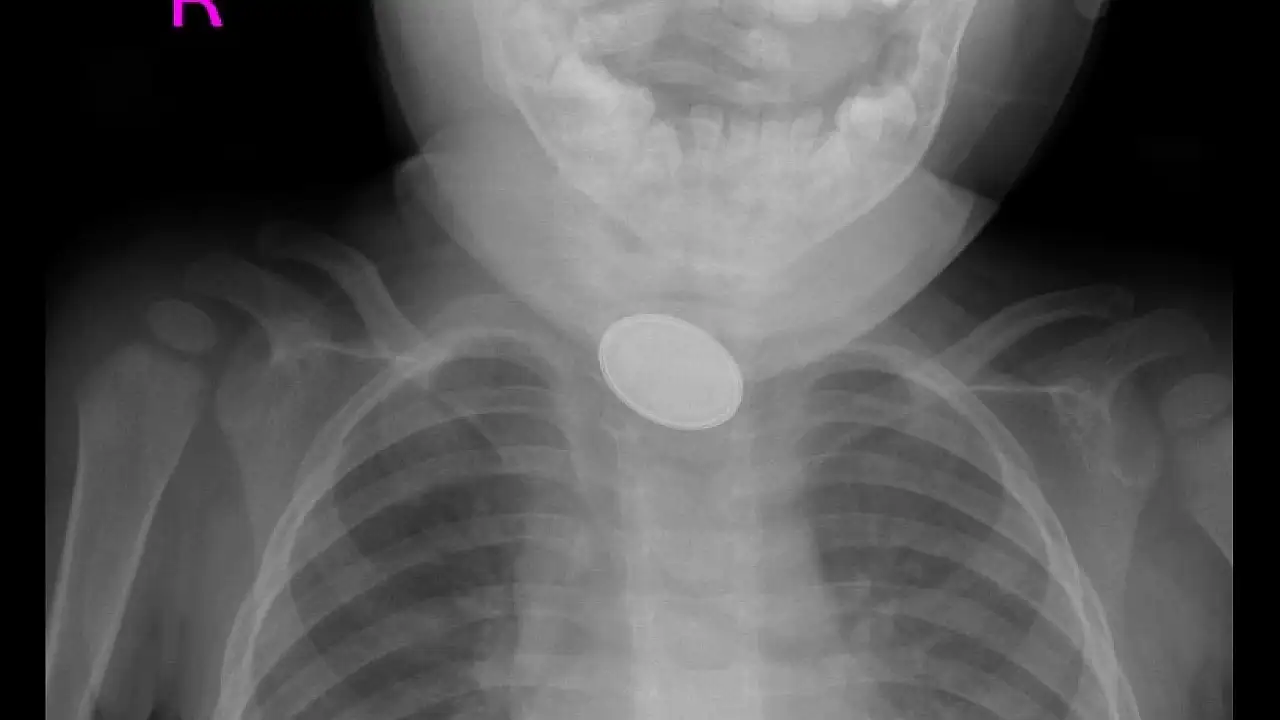

Kayseri'de 15 aylık A.Y.Ç.'nin yemek borusuna, evde oyun oynadığı sırada düğme pil ve lego oyuncak parçası kaçtı. O sırada yanında olan 4 yaşındaki kardeşi, 'Kardeşim lego yuttu' diyerek annesini çağırdı. A.Y.Ç.’nin ağızına bakan anne Tuğba Yılmaz, parçayı göremeyince dışkısından çıkacağını düşündü. Bir süre sonra A.Y.Ç.'nin yutma güçlüğü çektiğini gören Tuğba Yılmaz, Kayseri Şehir Hastanesi'ne başvurdu. A.Y.Ç.'ye yapılan röntgende, yemek borusunda düğme pil ve lego parçası oyuncağa rastlandı. Kız bebek A.Y.Ç., Kayseri Şehir Hastanesi Çocuk Cerrahisi ve Ürolojisi Anabilim Dalı Başkanı Doç. Dr. Mustafa Erman Dörterler ve ekibi tarafından ameliyata alındı. Yaklaşık 3 saatlik süren operasyonun ardından A.Y.Ç.'nin yemek borusuna kaçan düğme pil ile lego oyuncak parçası çıkarıldı.

Kayseri Şehir Hastanesi Çocuk Cerrahisi ve Ürolojisi Anabilim Dalı Başkanı Doç. Dr. Mustafa Erman Dörterler, "Hastamız 15 aylık bir bebek. Hastamız, disk pil ve beraberinde bir lego parçası yutmuş. Ben gece 01.30 gibi hastaneye geldim. Pili ve lego parçasını yutmasının üzerinden yaklaşık 6-7 saat geçmişti. Bu durumlarda dakika ve zaman çok önemli. 2 saatten sonra çok ciddi sıkıntılar oluşturabilecek hatta ölümle sonuçlanabilecek durumlarla karşı karşıya kalmaktayız. Ben, göğüs cerrahisi, çocuk gastroenteroloji, anestezi ekibi ve yardımcı sağlık personelleriyle beraber yaklaşık 20-25 kişiydik. Çocuğa, hızlı ve dikkatli bir şekilde müdahale ettik. Çünkü zaman ilerlediği için disk pil, yemek borusuna yapışmış ve delmek üzereydi. Dikkatli şekilde özenerek çıkarmaya çalıştık. Ekip çalışmasıyla beraber çıkarmayı başarabildik. Çocuğumuzun yoğun bakımdaki 2 günlük takip süreci devam ettikten sonra servisimize aldık. Şu an gayet iyi" diye konuştu.